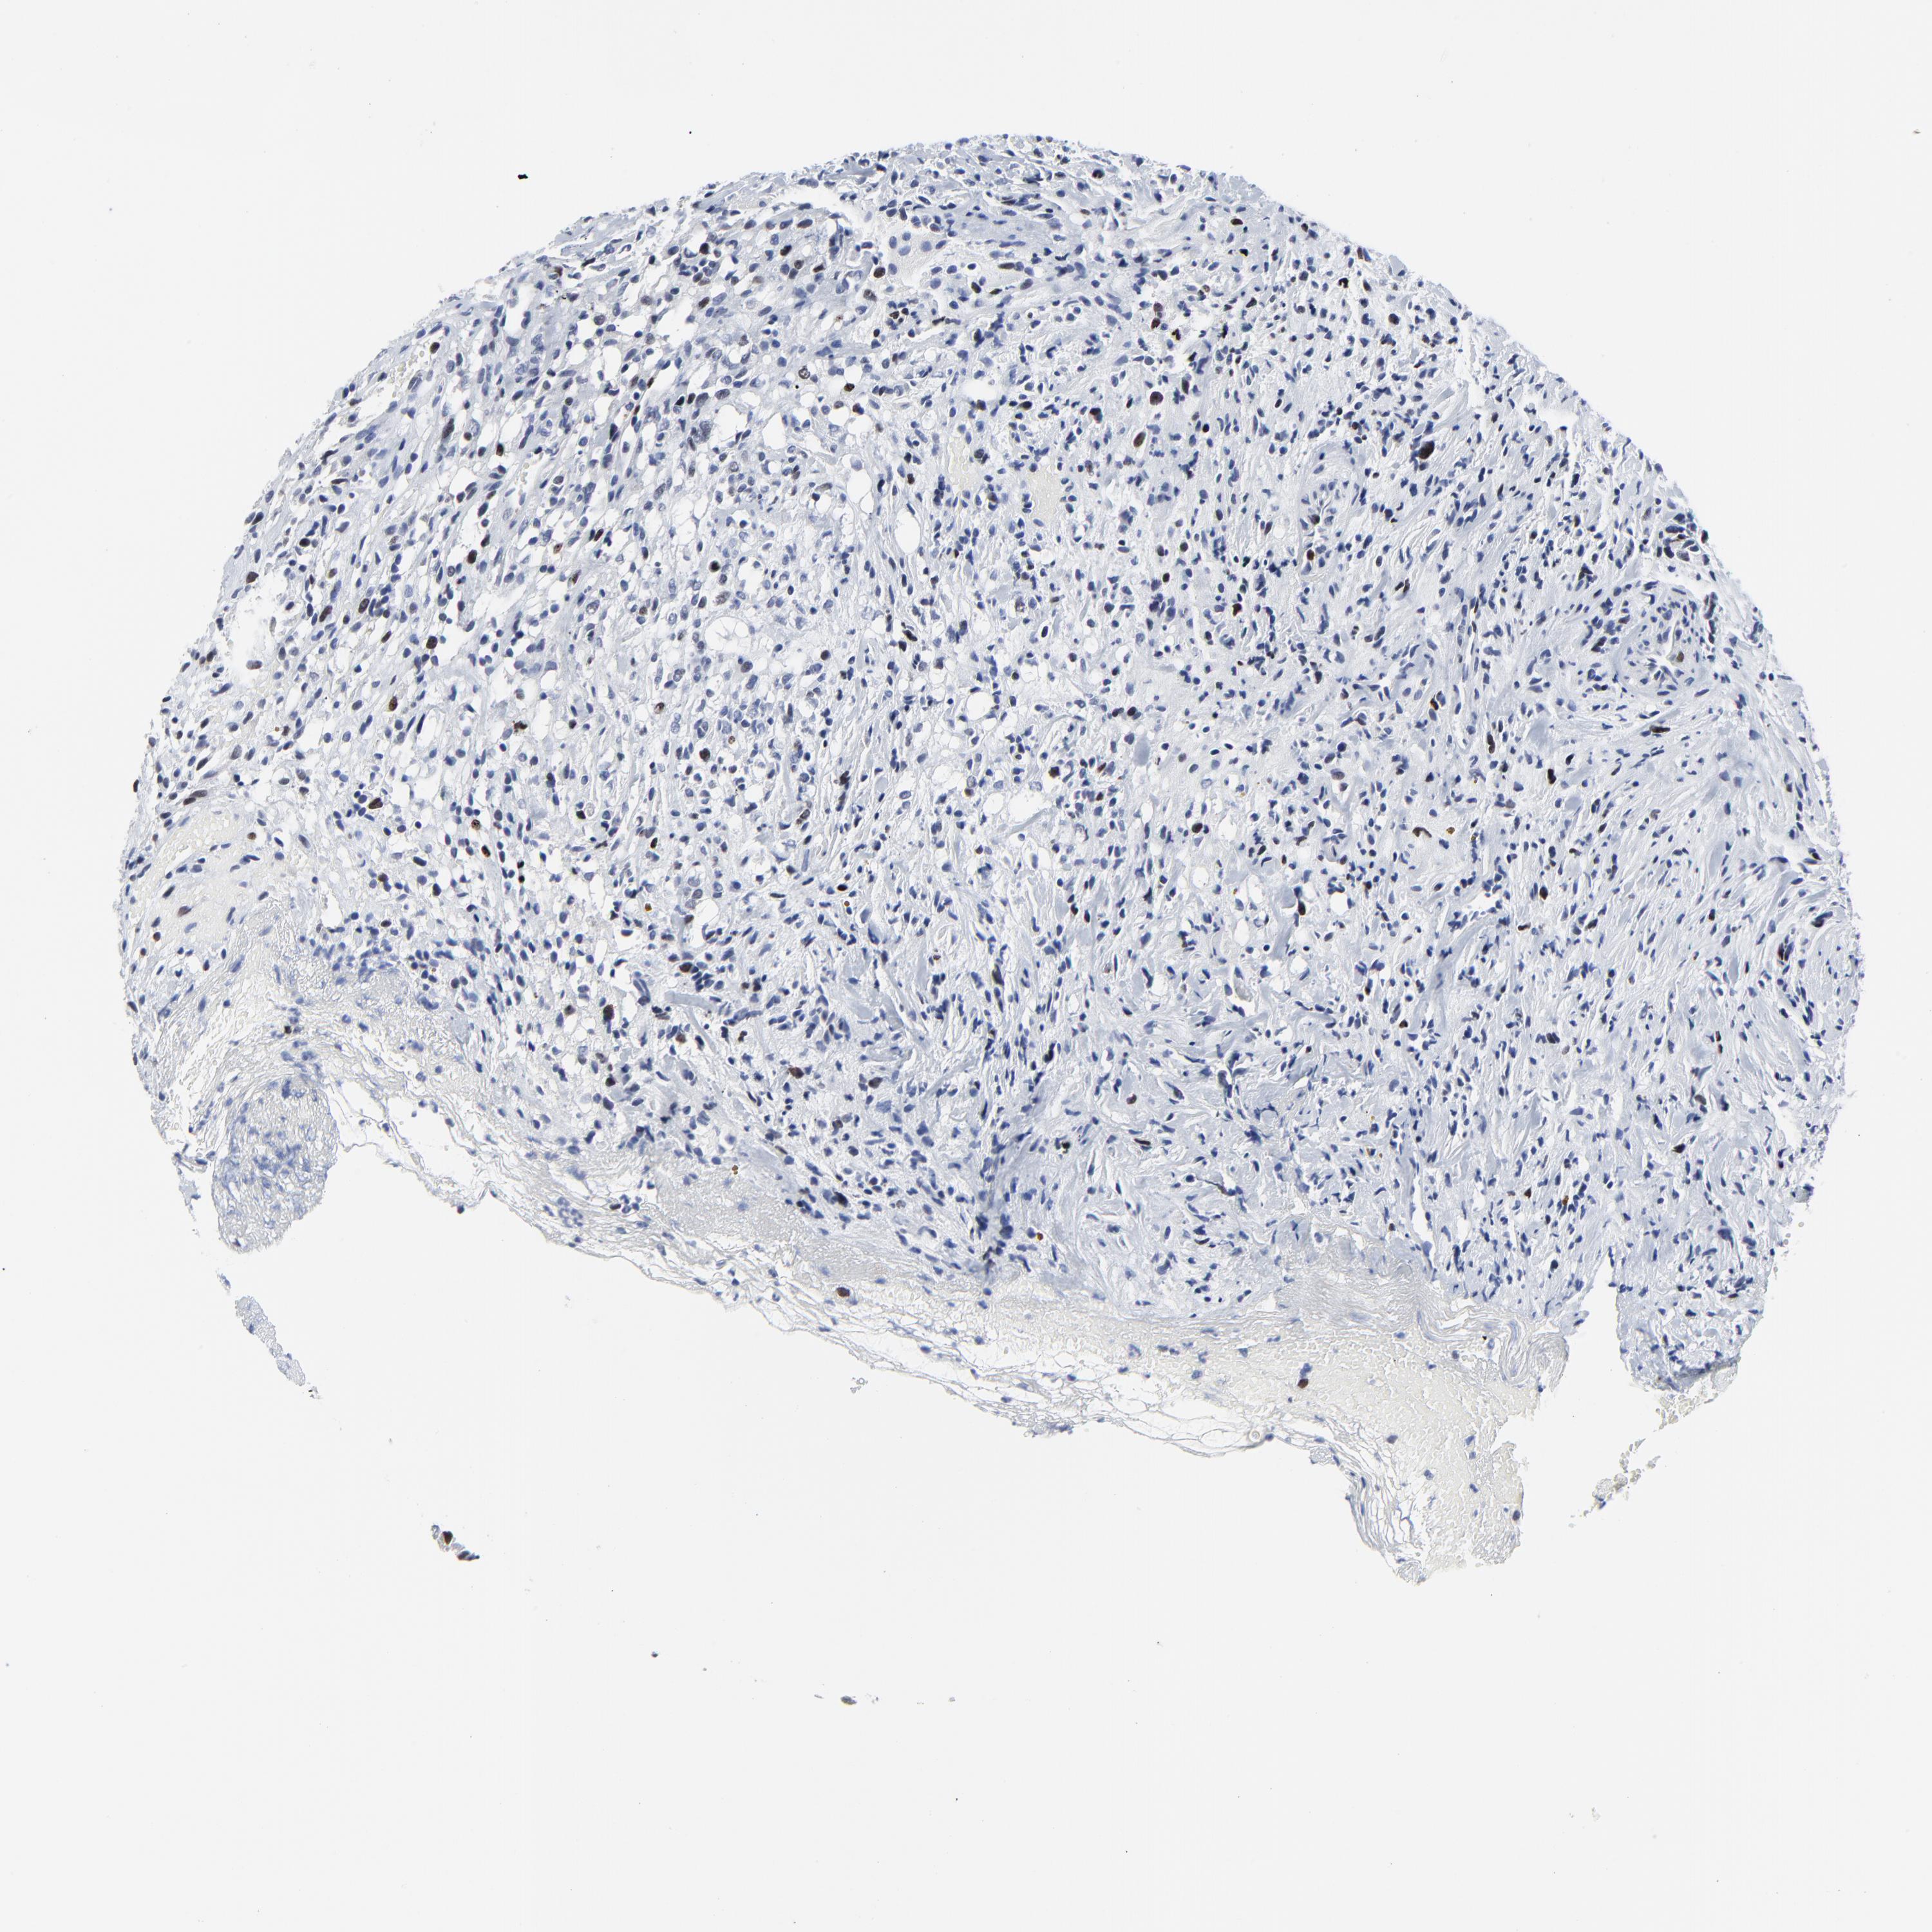

GLIOMA - Protein expressioni

A mouse-over function shows sample information and annotation data. Click on an image to view it in a full screen mode. Samples can be filtered based on level of antibody staining by selecting one or several of the following categories: high, medium, low and not detected. The assay and annotation is described here.

Note that samples used for immunohistochemistry by the Human Protein Atlas do not correspond to samples in the TCGA dataset.

Antibody stainingi

Antibody staining in the annotated cell types in the current human tissue is reported as not detected, low, medium, or high, based on conventional immunohistochemistry profiling in selected tissues. This score is based on the combination of the staining intensity and fraction of stained cells.

Each image is clickable and will lead to virtual microscopy that enables deeper exploration of all samples and also displays staining intensity scores, fraction scores and subcellular localization as well as patient and tissue information for each sample.

Antibody HPA003145

Staining

High

Medium

Low

Not detected

Intensity

Strong

Moderate

Weak

Negative

Quantity

>75%

75%-25%

<25%

None

Location

Nuclear

Cytoplasmic/membranous

Cytoplasmic/membranous,nuclear

Glioma, malignant, High grade

Glioma, malignant, Low grade